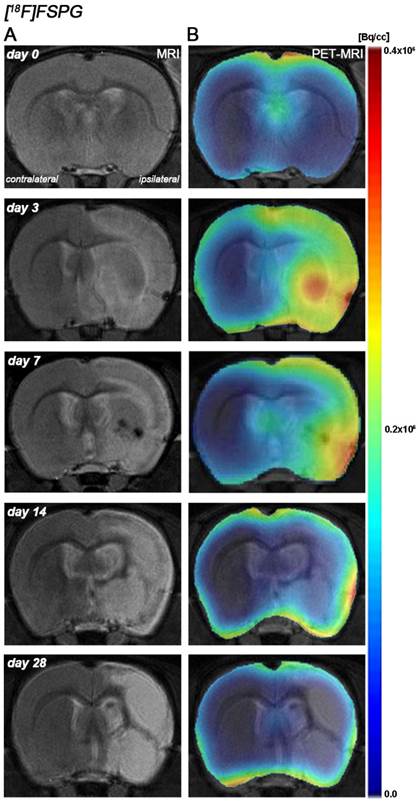

Hyperintensities of T2W images showed similar infarct extents as well as locations affected. All ischemic rats subjected to nuclear studies showed cortical and striatal MRI alterations (mean ± s.d. 344.49 ± 59.44 mm3, n=12) (Figure 1).

Figure 1

Magnetic resonance imaging (MRI) (T2-weighting (T2W)) and positron emission tomography (PET) images of [18F]FSPG at control (day 0), day, 3, day 7, day 14 and day 28 after middle cerebral artery occlusion (MCAO). Serial MRI (T2W) (A) and xc- system PET binding (B) images of coronal planes at the level of the lesion. PET images are co-registered with the MRI (T2W) of the same animal at different times to localize the PET signal. Images correspond to the lesion evolution of the same animal over time.

The coronal brain images with normalized color scale shown in Figure 1 illustrate the evolution of the [18F]FSPG-PET signals in ischemic animals at day 0 (control) and at 3, 7, 14 and 28 days after reperfusion. Quantification of the images provided information related to the time-course activity of system xc- in both the ipsilateral and contralateral cortex, in the striatum and the whole brain at days 0 (control) and 1, 3, 7, 14, 21 and 28 days after MCAO (Figure 2, n=6). All brain regions considered evidenced a similar [18F]FSPG binding evolution after long-term focal cerebral ischemia. In the ipsilateral whole brain (cerebrum), the PET signal for [18F]FSPG showed a non-significant increase at day 1 followed by a significant uptake increase from days 3 to 7 after ischemia in comparison to control (day 0) values (P<0.001, Figure 2A). In fact, the highest binding value was reached at day 3 after MCAO. Subsequently, the PET signal evidenced a progressive decrease from day 14 to day 28 compared to days 3 and 7. In the contralateral whole brain, [18F]FSPG PET signal at day 1 showed similar values to those at day 0 (control) followed by a non-statistically mild increase from days 3 to 7 compared to control values. This was followed by a progressive decline from days 14 to 28 after cerebral ischemia (Figure 2B). The cerebral cortex in the ipsilateral hemisphere evidenced a statistically [18F]FSPG PET signal progressive increase from day 1 to day 3 and 7 followed by a progressive decrease at days 14 and onwards (P<0.05; P<0.01, with respect to control animals, Figure 2C). In contrast, non-statistically significant differences were observed in the contralateral hemisphere despite the weak increase of PET signal observed from day 3 to day 7 following reperfusion (Figure 2D). Likewise, the non-ischemic cortex showed higher PET signal values than those observed in the non-infarcted striatum, however, this situation was reverted after cerebral ischemia where striatum displayed higher [18F]FSPG binding levels at days 3 and 7 after reperfusion than those observed in the cerebral cortex (P<0.001 with respect to control animals, Figure 2E).

PET imaging of system xc- with [18F]FSPG

Previous in vivo PET imaging of system xc- with [18F]FSPG evidenced a significant progressive increased uptake at early phase following MCAO in rats. Indeed, these results evidenced the role of system xc- on excitotoxic damage after reperfusion [4]. In the present study, [18F]FSPG binding was evaluated from day 1 to day 28 after MCAO in rats, to show its relationship to the neuroinflammatory reaction after cerebral ischemia. In the infarcted brain hemisphere, [18F]FSPG binding experienced a non-significant increase at day 1 followed by a maximum binding at days 3 to 7 that was followed by a progressive decline to pseudo-control values at days 21 to 28 after reperfusion (Figure 1 and 2). Nevertheless, these results stand in contrast with the in vivo PET imaging distribution of TSPO, a well-known marker for neuroinflammation, following cerebral ischemia [26, 38] (Figure 3). In our study, the ischemic brain hemisphere experienced a gradual [18F]DPA-714 binding increase from days 1 to 3 which peaked at day 7, followed by a slight decline afterwards. These results are in agreement with Martin and collaborators who, after monitoring the in vivo post-ischemic TSPO receptor expression with [18F]DPA-714 PET, observed a progressive binding increase that peaked at day 11 followed by a progressive decline later on [26]. Likewise, the peak of the inflammatory reaction observed by PET imaging during the first week after ischemia runs in parallel with the gradual recovery of neurological handicap (Figure 3L). Thus, animals experienced a quasi-recovery of functional outcome one month after stroke. Likewise, such capacity to undergo motor and cognitive recovery has been monitored in adult human brain following stroke [39].